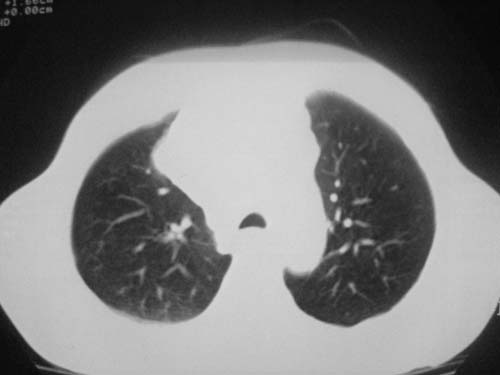

以下是引用科室第一人在2010-3-25 20:30:00的发言:[br]1:纵膈肿瘤性病变,恶性胸腺瘤可能性大伴纵膈右肺门淋巴结转移,右侧胸腔积液。[br]2:右侧肺门肿瘤性病变,纵膈淋巴结转移,右侧胸腔积液。右下叶转移。

以下是引用子期在2010-3-25 21:00:00的发言:[br]先考虑右中央型肺癌伴转移。

以下是引用江广1996在2010-3-25 22:49:00的发言:[br]通常肺癌向纵隔转移多见,纵隔肿瘤向肺内转移少见(有的表现为向肺内侵润)。本例以一元论考虑:右中心型肺癌并纵隔淋巴等多处转移。[br][br][本贴已被 江广1996 于 2010-3-25 22:50:07 修改过]

以下是引用yangyudong333在2010-3-26 6:43:00的发言:[br]“冰冻纵膈”,考虑纵膈淋巴瘤伴肺内及胸膜侵润。